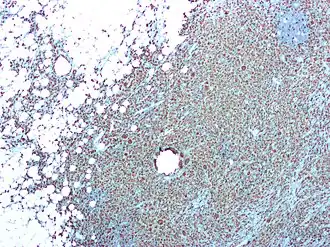

Патологическая анатомия

Гематогенный пиелонефрит

При гематогенном пиелонефрите (инфекция попадает через кровь) воспалительные очаги расположены преимущественно в корковом веществе, вокруг внутридольковых сосудов. Воспалительный процесс, захватывая интерстициальную ткань, повреждает главным образом тубулярную систему(канальцы). При уриногенном, восходящем пиелонефрите инфекция поражает почку отдельными очагами, веерообразно, в виде клиньев, простирающихся от лоханки до поверхности почки. Между этими очагами воспаления и последующего фиброза расположены участки нормальной почечной ткани. При двустороннем пиелонефрите патологический процесс в почках распространяется неравномерно, асимметрично в противоположность гломерулонефриту и нефросклерозу.

Острый пиелонефрит

Пиелонефрит, являясь вначале очаговым процессом, с каждой новой атакой принимает диффузный характер. Интерстициальная ткань играет весьма важную физиологическую роль в межклеточном обмене веществ. После исчезновения воспалительных инфильтратов в ней не происходит истинного восстановления промежуточной ткани; на месте погибших элементов почечной паренхимы развивается рубцовая ткань. Первичный и вторичный острый пиелонефрит могут протекать вначале в виде серозного, затем гнойного интерстициального воспаления. С учётом этого принято пользоваться терминами «острый серозный пиелонефрит» и «острый гнойный пиелонефрит». В то время как острый серозный пиелонефрит наблюдается в 64 %, острый гнойный — только у 36 % больных острым пиелонефритом. В стадии острого серозного воспаления почка увеличена, напряжена. Паранефральная клетчатка значительно отёчна. Микроскопически в межуточной ткани обнаруживаются многочисленные периваскулярные инфильтраты. Под влиянием соответствующего лечения эта стадия претерпевает обратное развитие, но серозный острый пиелонефрит может перейти и в стадию гнойного воспаления.

Острый гнойный пиелонефрит встречается в виде апостематозного нефрита, абсцесса и карбункула почки. Апостематозный нефрит — это метастатический нагноительный процесс, одна из последующих стадий острого пиелонефрита. При этом корковое вещество почки как на поверхности, так и на разрезе усеяно мелкими гнойниками, имеющими вид бисера.

Апостематозный нефрит

При апостематозном нефрите почка увеличена, серо-вишнёвого цвета. Околопочечная клетчатка резко отёчна. После снятия фиброзной капсулы видны множественные мелкие (размером от булавочной головки до горошины) абсцессы, расположенные одиночно или группами. На разрезе почки мелкие абсцессы часто находят и в мозговом веществе. Микроскопически в интерстициальной ткани выявляются множественные очаги гнойного воспаления. В окружности мальпигиевых клубочков видны скопления мелкоклеточных инфильтратов с очагами некроза. Мочевые канальцы сдавлены инфильтратами, которые расположены как в межуточной ткани, так и в периваскулярных пространствах.

Апостематозный нефрит в 23 % случаев сочетается с карбункулом почки. Эти два вида гнойного поражения почки представляют собой единый патологический процесс, проявляющийся лишь в разной последовательности и интенсивности своего развития. Если для апостематозного нефрита характерны множественные мелкие абсцессы, то для карбункула почки — локализованный нагноительный очаг, отличающийся опухолевидным прогрессирующим ростом воспалительной инфильтрации без наклонности к большому абсцедированию. По внешнему виду такой процесс в почке весьма напоминает карбункул кожи. Это обстоятельство и дало основание Israel в 1891 г. назвать данное заболевание карбункулом почки.

Размеры карбункула колеблются от 0,3 до 2 см, редко больше. Карбункул бывает одиночным и множественным, в 25 % случаев сочетается с апостематозным нефритом. Обычно гнойный процесс поражает одну почку, редко — обе (5 %). При благоприятном течении острого гнойного пиелонефрита происходят рассасывание инфильтратов и разрастание на их месте соединительной ткани. Замещение гнойных очагов соединительной тканью ведёт к образованию на поверхности почки рубцовых втяжений вначале тёмно-красного, а затем бело-серого цвета. На разрезе почки эти рубцы имеют форму клина, доходящего до лоханки.

- Итак, при остром пиелонефрите воспалительный процесс вначале локализуется в межуточной ткани, а затем в него вовлекаются канальцы и в последнюю очередь клубочки. При переходе процесса в хроническую стадию возникают продуктивный эндартериит, гиперплазия средней оболочки сосудов и склероз артериол. Склероз артериол служит одной из причин дальнейшей атрофии почки.

В группе хронического пиелонефрита при анализе материала биопсий коркового вещества почки различают 6 морфологических вариантов. Нет достаточных оснований рассматривать все из них как последовательные стадии изменений — правильнее считать их неодинаковыми формами течения хронического пиелонефрита[5], обусловленными различиями факторов, способствующих развитию пиелонефрита.